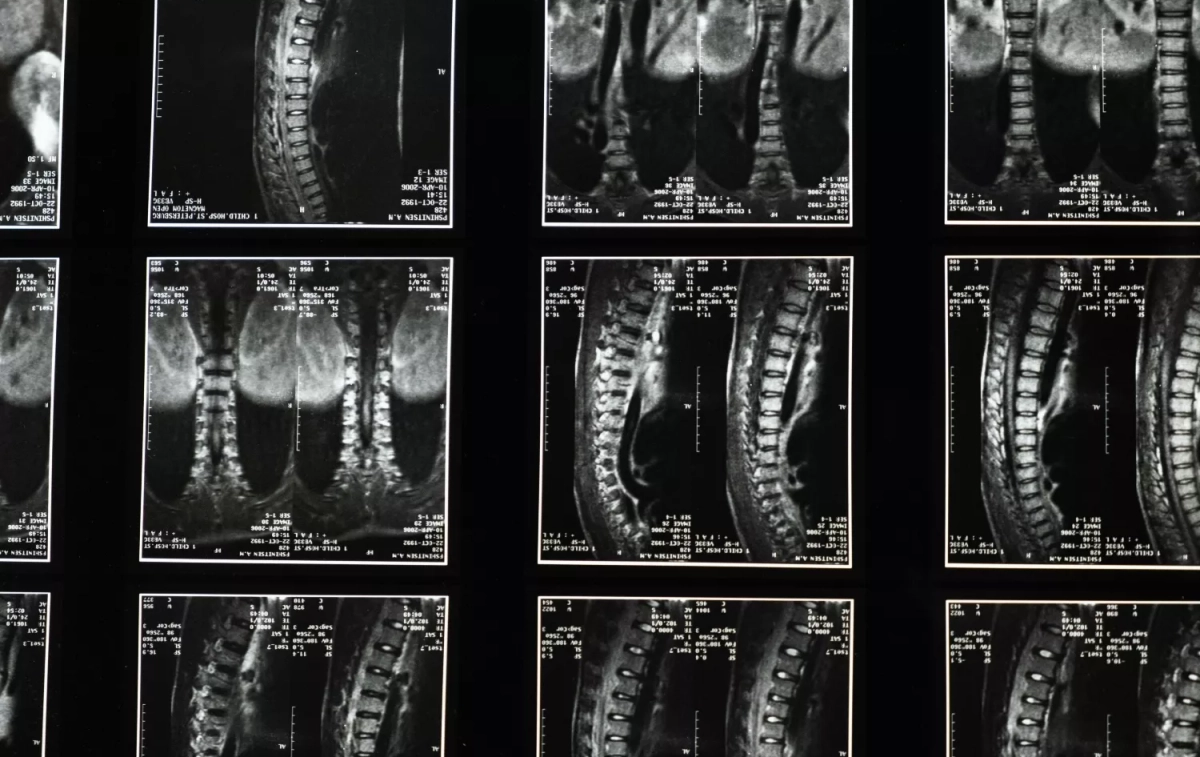

“La densitometría nos ha permitido medir la densidad ósea, y nos indica que hay riesgo de fractura cuando la densidad es inferior a un 40% respecto al hueso sano (-2.5 desviaciones estándar)”, explica. “Es muy importante el diagnóstico antes de que se produzca una fractura, sobre todo, si ya se ha padecido una, pues la posibilidad de sufrir posteriores es más elevada”, subraya.

“En el caso de la osteoporosis senil los síntomas pueden ser la pérdida de altura, un aumento de la curvatura de la espalda que produce una cifosis y, si ésta es muy pronunciada, puede crear dificultades al caminar”, expone Alegre de Miquel. “Las fracturas más comunes son la de la muñeca (fractura de Colles), las de las vértebras y las de cuello de fémur”, especifica.